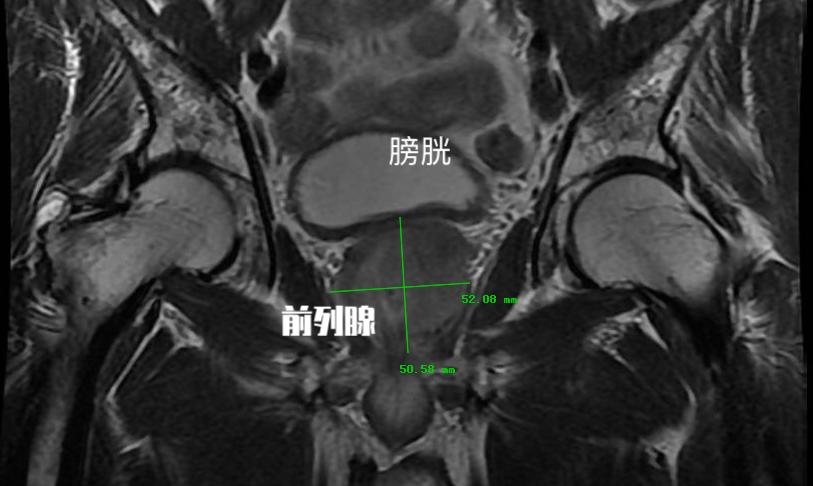

前列腺增生顾名思义就是前列腺的体积增加,这是前列腺增生在解剖学上的表现之一。一般我们将患者初次就诊的前列腺体积定义为基线。 研究证实基线前列腺体积与前列腺增生临床进展显著相关。 大部分的研究都将这个 体积定义在30ml(前列腺体积=0.52*左右径*前后径*上下径)。前列腺体积超过30ml的患者需要药物或手术治疗的可能性将提高4倍!

前列腺增生临床进展危险因素四:前列腺膀胱内突出度

这是一个彩超检查经常会报的指标,但是往往会被患者和医生所忽视。 前列腺膀胱内突出度是超声测得的前列腺矢状面下突入膀胱内的前列腺尖端至膀胱与前列腺交界平面的距离。 这是用于预测膀胱出口梗阻的重要指标。 这个突出程度越重,患者往往临床症状越重,同时需要手术治疗的可能性也越高!